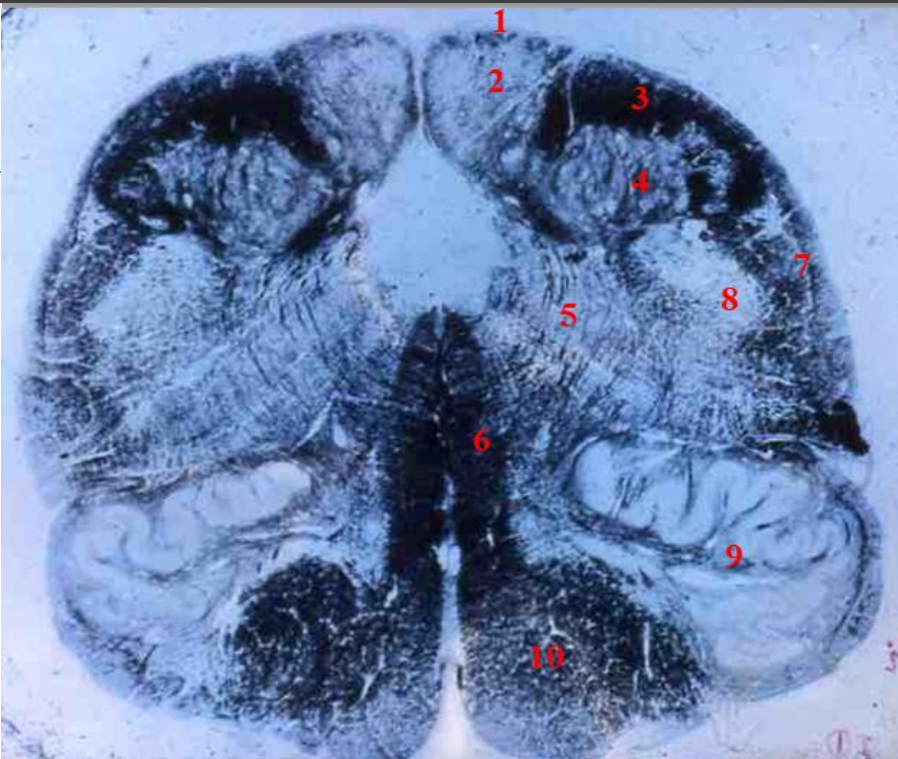

1

lumbar cord

- fibre tracts are few

- large anterior and posterior horns due to lumbar plexus

fasciculus gracilis

How well did you know this?

Not at all

2

3

4

5

Perfectly

Q

A